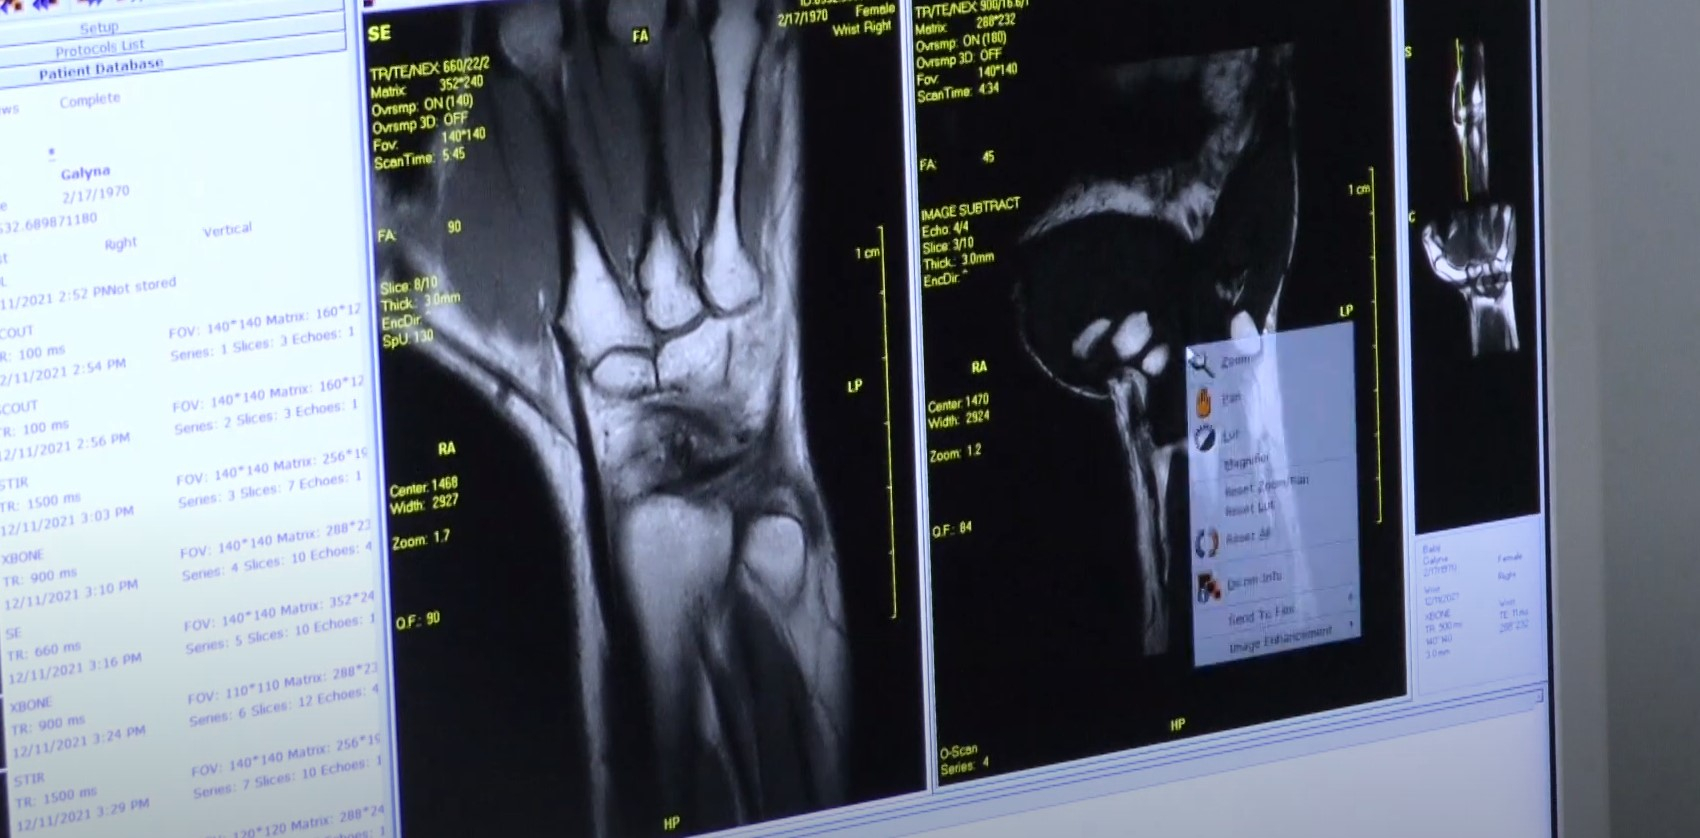

Додаткова безпека: івано-франківська міська клінічна лікарня №1 отримала новий МРТ-апарат (ВІДЕО)

Івано-Франківська міська клінічна лікарня №1 отримала новий МРТ-апарат.  На обладнання чекали давно, розповідають медики, адже це нові можливості для обстеження та лікування пацієнтів.

МРТ-апарат куплений за кошти місцевого та державного бюджетів. Також   в перспективі тут планують модернізувати відділення травматології.